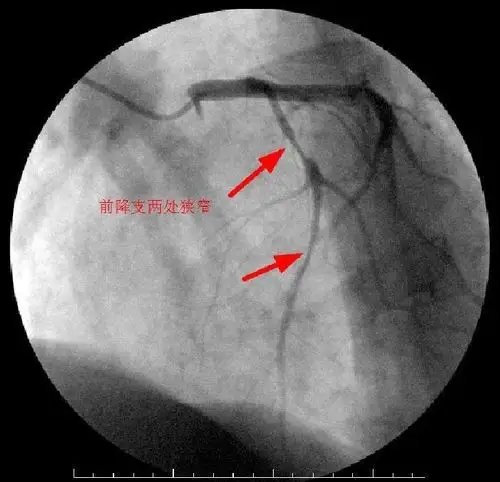

冠脉造影术——叶县二院介入科

冠状动脉造影

冠状动脉造影,左冠状动脉造影

正常冠脉造影和冠状动脉支架植入术图解